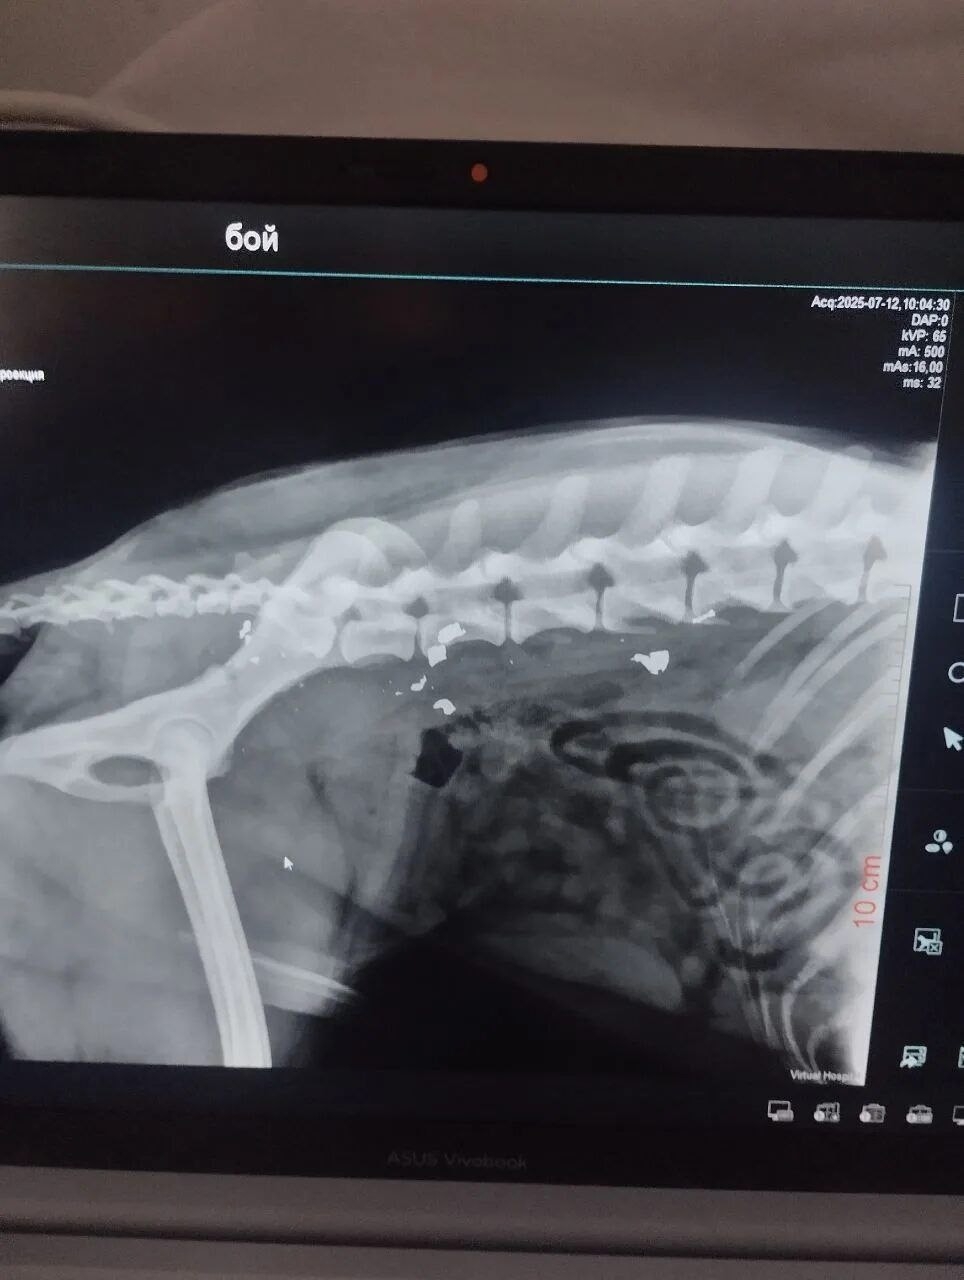

СРОЧНО! ОН ГНИЕТ ЗАЖИВО! 🆘 Щенка расстреляли еще летом, и всё это время он медленно умирает.

Когда-то Боя уже возили в Волгоград на рентген, но полноценного лечения он не получил и снова оказался на улице. Итог — инвалидность и гниющая заживо конечность.